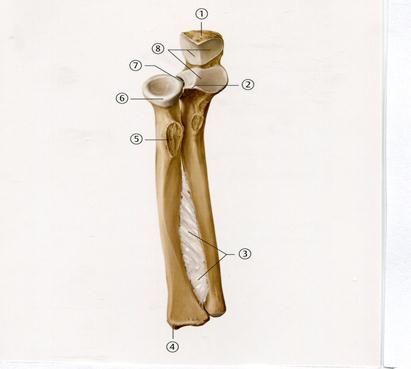

48. Төменде көрсетілген суреттегі белгіленген № 4 анатомиялық құрылымды атаңыз.

А. Акромиальді өсінді

+В. Кіші төмпешік

С. Құстұмсық тәрізді өсінді

D. Төмпешікаралық жүлге

Е. Үлкен төмпешік

+Е. Шынтақ сүйек

52. Төменде көрсетілген суреттегі белгіленген № 1 бұлшықетті атаңыз.